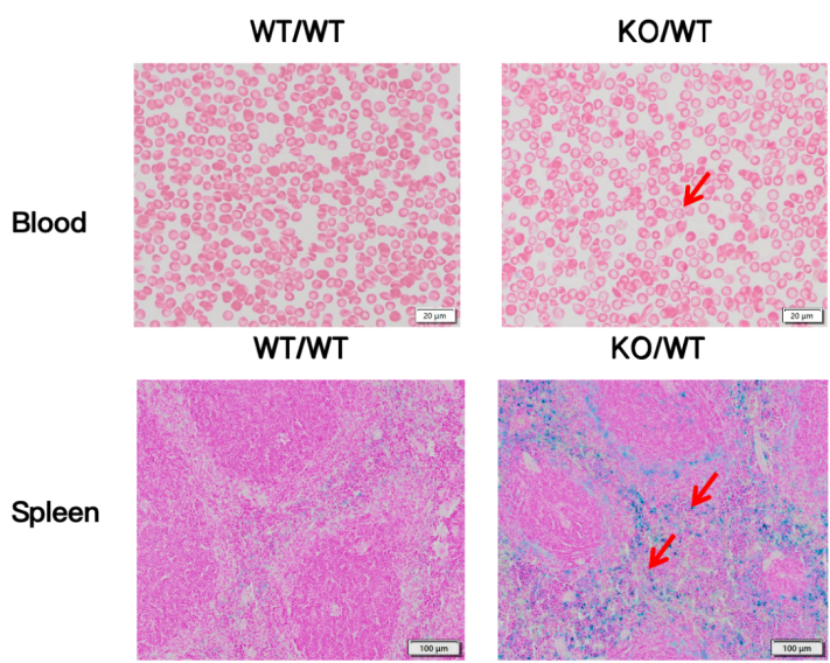

集萃药康采用CRISPR/Cas9基因编辑技术敲除了小鼠两个α珠蛋白基因Hba-a1和Hba-a2,建立α-珠蛋白双基因敲除小鼠模型。通过血常规检测发现,与野生型小鼠相比,Hba-a1&Hba-a2-dKO杂合小鼠的HGB (Hemoglobin, 血红蛋白浓度)、MCV (Mean Corpuscular Volume, 平均红细胞体积)和MCH (Mean Corpuscular Hemoglobin, 平均红细胞血红蛋白含量)显著降低,RETIC (Reticulocyte Count, 网织红细胞比率)显著升高(图1),血涂片吉姆萨染色进一步证实红细胞形态异常,明显畸形、染色质不均,部分红细胞碎裂溶解,普鲁士蓝染色结果显示杂合小鼠脾脏中有过量铁沉积(图2),完美再现患者的典型病理特征。

图2 Hba-a1&Hba-a2-dKO小鼠血涂片染色分析及普鲁士蓝染色分析

杂合β-地贫小鼠的外周血涂片可见红细胞形态异常,明显畸形、染色质不均,部分红细胞碎裂溶解,显示典型的重度地贫患者血液学形态学特征。同时,普鲁士蓝染色显示这些小鼠的脾脏以及肝等器官内有大量铁沉积(图8)。该模型为深入探索β-地贫病理机制及新药筛选提供了重要支持。

图8 Hbb-bs & Hbb-bt-dKO小鼠血涂片染色分析及普鲁士蓝染色分析